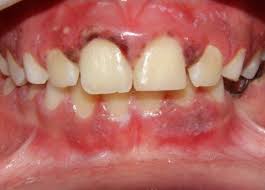

A gengivite necrosante, também chamada de gengivite ulcerativa necrosante (GUN), é uma doença periodontal aguda caracterizada por um processo inflamatório destrutivo que acomete principalmente as papilas interdentais.

Seu quadro clínico é marcado pela presença de necrose tecidual, halitose fétida, dor aguda e sangramento espontâneo.

- Gengivite ulcerativa necrosante (GUN): apresenta necrose das papilas interdentais, pseudomembranas acinzentadas e dor intensa. É considerada a forma inicial das doenças periodontais necrosantes.

O sinal mais marcante é a necrose das papilas interdentais, frequentemente descrita como uma aparência em “cratera”, resultado da destruição tecidual localizada. Sobre essas áreas necrosadas, observa-se a formação de pseudomembranas acinzentadas ou esbranquiçadas, que recobrem as lesões e podem ser facilmente removidas, revelando um tecido subjacente intensamente dolorido e sangrante.

A dor é outro sintoma predominante, de caráter agudo e muitas vezes desproporcional ao estímulo, tornando atividades rotineiras, como a mastigação ou até mesmo a higienização oral, extremamente desconfortáveis.

O sangramento gengival ocorre de forma espontânea ou ao mínimo contato, refletindo o grau de inflamação e fragilidade vascular local.

Associado a isso, a presença de halitose fétida é quase constante, consequência da necrose tecidual e da atividade metabólica de microrganismos anaeróbios, sendo um sinal de alerta perceptível tanto ao paciente quanto ao profissional.